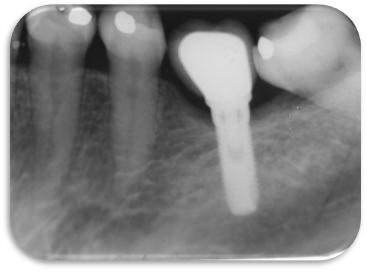

Imagem do artigo

Figura 4. Radiografia panorâmica dos implantes antes do início da etapa protética – baseline.  Este exame é ideal para observar o posicionamento da plataforma do implante com relação à crista óssea distal e mesial. Observar ainda o correto posicionamento dos implantes HI (nível ósseo).